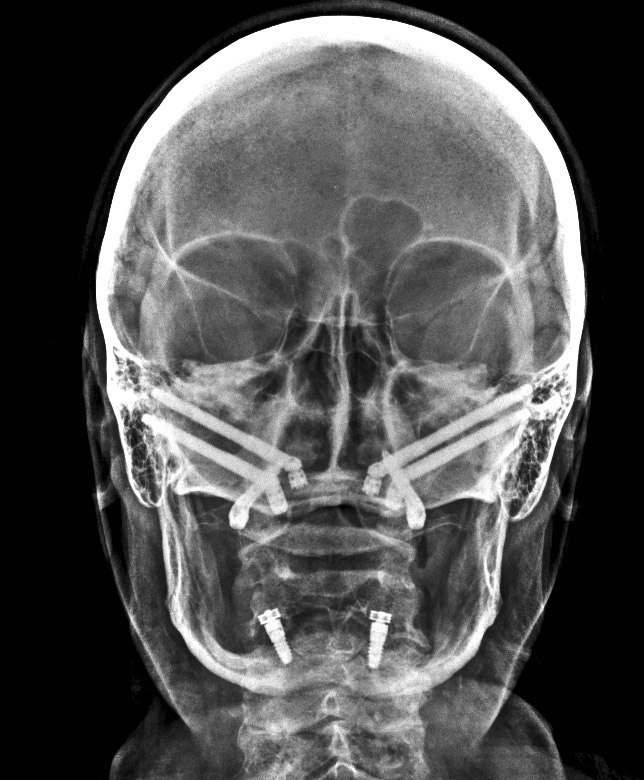

Mario Venturini, director del Instituto de Cirugía Maxilofacial en Rosario, Argentina, nos cuenta el tema que impartirá en la Jornada Virtual de Implantología de AIOI, que versará sobre “Implantología con anclaje extramaxilar”, técnica que permite reconstituir el arco dentario completo del paciente.

La implantología impulsó una mejora en la calidad de vida de los pacientes, mejorando notablemente no solo su confort y estética sino también su autoestima. Aunque pareciera poco y no lo es, evitó dañar más piezas dentarias para lograr un mismo resultado. Si todo ello es cierto, válido y genuino, el anclaje extramaxilar vino más aún, hace ya tiempo, a dar otro gran salto en la resolución quirúrgico protésica en un sesgo de pacientes que seguían excluidos de los beneficios de la implantología por razones obvias: carecían de stock óseo donde implantar.

La implantología volvió a los pacientes más ambiciosos y demandantes de importantes rehabilitaciones, y con justa razón. Hoy en día, prácticamente no hay límites ni etarios ni resortivos-resectivos en los cuales no pueda lograrse la mayor de las rehabilitaciones, el mayor gold estándar, al que los pacientes pueden aspirar: me refiero, ni más ni menos, que a reconstituir su arco dentario completo fijo. Incluso con la posibilidad de remoción y mantenimiento que un simple mortal no implantado no tiene.